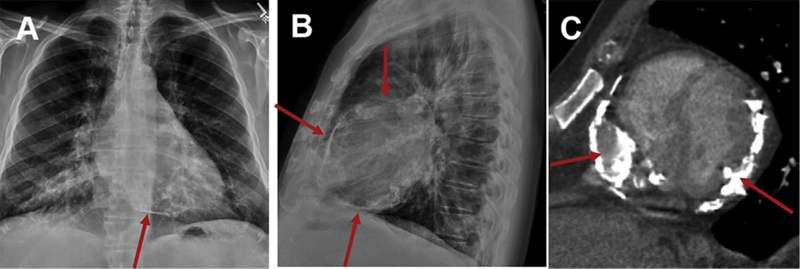

Trong cơ thể canxi được lưu trữ nhiều nhất ở xương và răng, trong máu cũng có một lượng nhỏ canxi nhưng chỉ chiếm 1% tổng lượng canxi của cơ thể. Vôi hóa mạch máu là hiện tượng các mảng tích tụ canxi hình thành và kết tủa theo thời gian tạo thành những mảng ở thành mạch, đây được xem là một dạng của bệnh xơ vữa động mạch. Một nguyên nhân khác được biết đến là do quá trình lão hóa tự nhiên của cơ thể khiến mạch máu bị suy giảm độ đàn hồi. Hiện tượng vôi hóa thường xảy ra ở nơi có lưu lượng tuần hoàn cao như các động mạch, màng ngoài tim, thận, não, tuyến vú,...

Các mảng tích tụ canxi phình sâu vào lòng mạch làm cản trở dòng máu chảy và giảm lượng máu tưới cho các cơ quan. Khi lòng mạch máu hẹp đến hơn 70% thì cũng được xem như là tắc mạch, vì lượng máu chảy qua chỗ quá hẹp, không đủ nuôi dưỡng các mô mà nó chi phối.

Lòng mạch gồ ghề vì các mảng tích tụ canxi lồi vào trong, làm cho các tiểu cầu dễ bám dính vào và kích hoạt quá trình đông máu trong cơ thể. Đây là một chuỗi phản ứng dây chuyền tạo nên cục máu đông trong lòng mạch.

Cục máu đông nếu đủ lớn sẽ làm tắc mạch ngay tại chỗ, nếu không nó sẽ bị dòng máu với áp lực đủ lớn đẩy trôi theo đường đi của mạch. Mà càng xa tim đường kính của các mạch máu càng nhỏ, cuối cùng gây tắc ở mạch máu một đoạn nào đó.

Tắc mạch có thể xảy ra ở bất kỳ đoạn nào trên đường đi của dòng chảy máu, nhưng nguy hiểm nhất là tắc mạch vành tim và tắc mạch não, gây nhồi máu cơ tim và nhồi máu não, dẫn đến phần mô do nhánh bị tắc chi phối không được nuôi dưỡng và dần hoại tử.